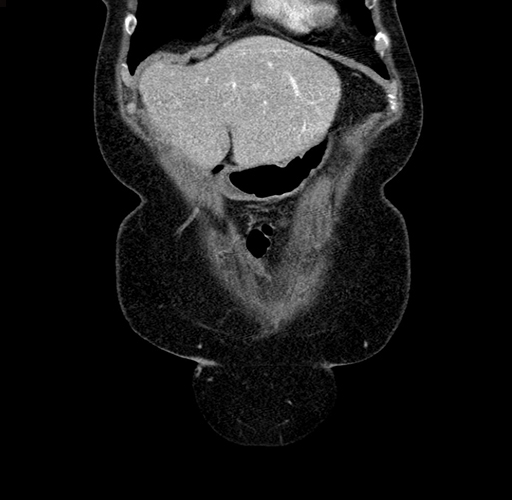

Pre-Chemo: Coronal Venous

Coronal Venous